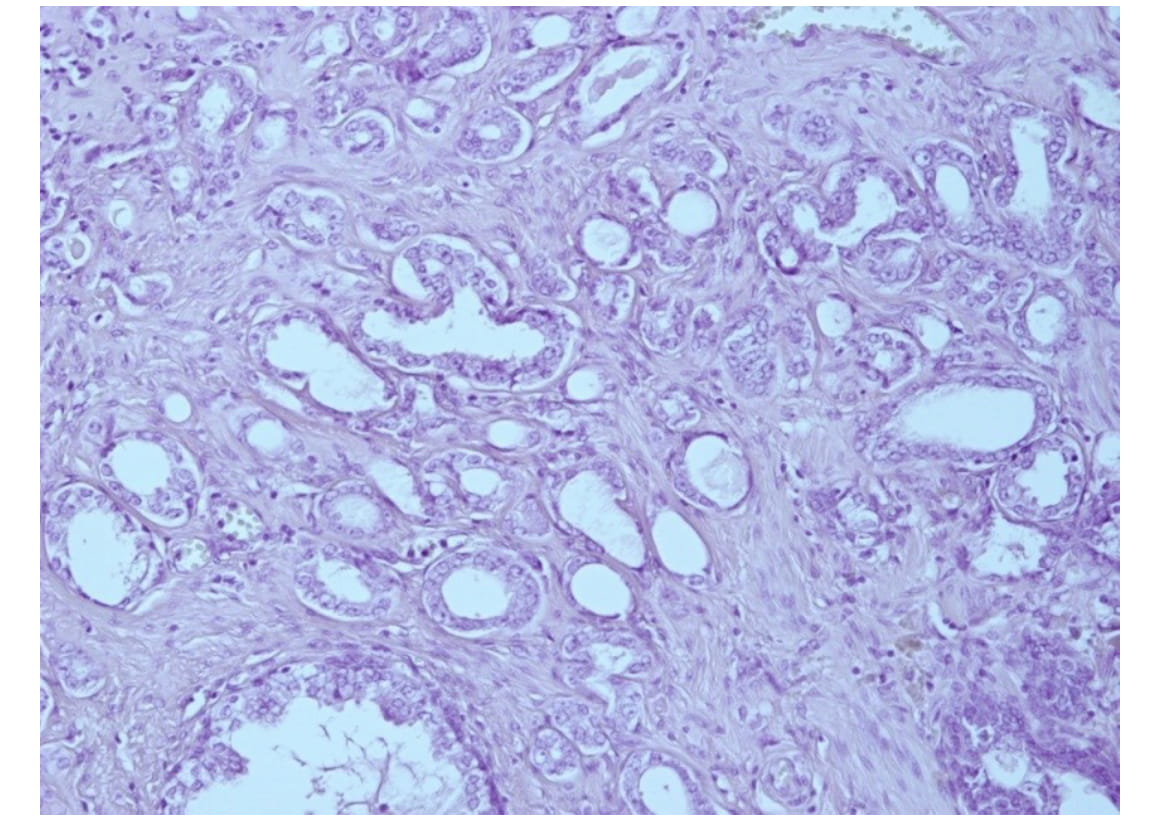

In 80 of 85 patients included into the study (94.1%), the histological type of the neoplasm was acinaradenocarcinoma, in 5 patients (5.9%) rare forms of PC were found (Fig. 1).

Fig. 1. Acinaradenocarcinoma of prostate. Gleason score 4. Staining with hematoxylin and eosin, x200